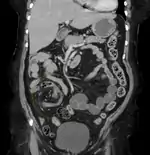

Volvulus with gangrene of the sigmoid

Sigmoid

Treatment for sigmoid volvulus may include sigmoidoscopy. If the mucosa of the sigmoid looks normal and pink, a rectal tube for decompression may be placed, and any fluid, electrolyte, cardiac, kidney or pulmonary abnormalities should be corrected. The affected person should then be taken to the operating room for surgical repair. If surgery is not performed, there is a high rate of recurrence.[10]

For people with signs of sepsis or an abdominal catastrophe, immediate surgery and resection are advised.